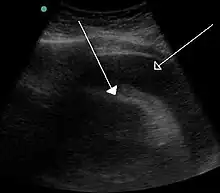

| |

| A very large pericardial effusion resulting in tamponade as a result of bleeding from cancer as seen on ultrasound. Closed arrow – the heart; open arrow – the effusion | |